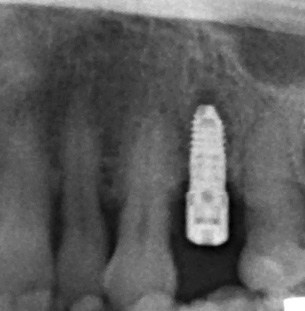

Grazie a dima e drivers, la chirurgia guidata consente una fresatura biologicamente incrementale come con un protocollo convenzionale; l’osso autologo raccolto durante la fresatura può essere utilizzato come particolato da innesto al bisogno. I dati clinici e demografici raccolti includono età, sesso, storia clinica e terapie farmacologiche in atto. I dati correlati agli impianti includono, invece, localizzazione anatomica, diametro, lunghezza, torque di inserzione, tipo di protesi, e parametri ossei rilevati alla diagnosi (Figure 2-3). Nel corso del follow-up sono stati registrati la sopravvivenza implantare protesica e il livello di osso marginale. I dati sono stati registrati da un esaminatore indipendente.

Le OPT a posizionamento del paziente standardizzato sono state eseguite alla consegna della protesi (3 mesi per la mandibola, 6 mesi per la maxilla) e a 1,3, 6 e 12 mesi dopo il carico. Le radiografie sono state calibrate con ImageJ utilizzando l’impianto di lunghezza conosciuta per correggere la magnificazione, mentre la perdita d’osso marginale è stata misurata dalla spalla dell’impianto al primo punto di contatto tra osso e impianto. Il dato principale è la perdita di osso marginale mesiale e distale; i dati secondari sono invece la sopravvivenza degli impianti e le complicazioni chirurgiche/protesiche. Il test di Shapiro-Wilk verifica la normalità; le variabili qualitative sono riassunte in base alla frequenza, mentre le variabili quantitative in base a media e deviazione standard. La sopravvivenza è analizzata con lo stimatore di Kaplan-Meier utilizzando il software SPSS v15.0 (Statistical Package for Social Science versione 15.0).

Il 20% degli impianti è stato posizionato nella mandibola (per lo più in posizione 47) e il restante 80% nel mascellare superiore (il 20% in posizione 16 e il 20% in posizione 25). Gli impianti posizionati nel mascellare superiore hanno trovato un osso tipo IV, mentre gli impianti posizionati nella mandibola hanno trovato un osso tipo III. Gli impianti utilizzati hanno un diametro compreso tra 4.0 e 4,5 mm (il 66.7% sono da 4.0 mm) e una lunghezza compresa tra 4.5 mm e 7.5 mm (il 53.3% sono lunghi 7.5 mm). Nell’86.7% dei casi non è stato eseguito alcun procedimento chirurgico aggiuntivo; in un caso, due impianti hanno previsto in rialzo di seno transcrestale con PRGF-Endoret e osso autologo. Nel 93.3% dei casi la protesizzazione ha previsto ponti avvitati a più elementi; un impianto è stato protesizzato mediante elemento singolo avvitato con componente transepiteliale. Il follow-up medio è stato di 12.4 ± 1.05 mesi dal carico. Il 100% degli impianti è sopravvissuto, senza complicanze né chirurgiche né protesiche. La perdita di osso media a 12 mesi è stata mesialmente di 0.15 ± 0.74 mm e distalmente di 0.13 ± 0.85 mm. La Figura 4 mostra l’osso perso su un singolo impianto e le Figure 5-14 illustrano un caso clinico rappresentativo.